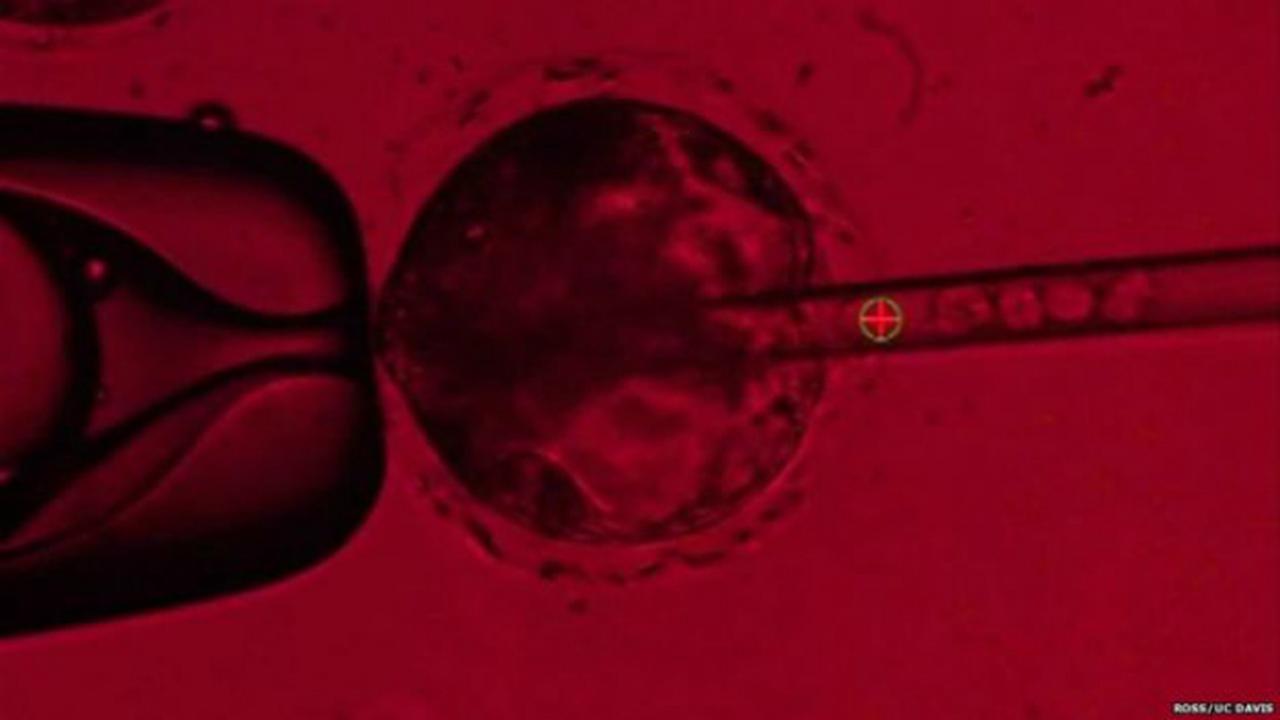

Liputan6.com, Jakarta Perizinan laboratorium produksi sel punca rupanya masih terkendala. Padahal, inovasi pengobatan dengan sel punca dinantikan banyak pasien yang membutuhkan.

"Untuk sel punca, kami sudah sampai tahap uji klinis. Laboratorium produksi sudah ada, tapi masih ada masalah (terkendala) perizinannya," kata Dekan Fakultas Kedokteran Universitas Indonesia, Ari Fahrial Syam saat sesi bincang-bincang Dialog Kinerja 3 Tahun Badan POM di Kantor BPOM, Jakarta, Senin (22/7/2019).

Masalah perizinan laboratorium sel punca disampaikan langsung Ari di hadapan Kepala Badan Pengawas Obat dan Makanan Penny K Lukito. Uji klinis sel punca sudah diikuti 200 pasien.

"Ini sangat bermanfaat bagi pasien yang ikut uji klinis. Apalagi pasien yang punya masalah pengapuran dan ortopedi. Misalnya, tulangnya enggak bisa tersambung," lanjut Ari.

"Sel punca juga bermanfaat pada pasien gagal ginjal kronis dan kelumpuhan saraf. Ini (laboratorium) akan sangat men-support (mendukung produksi) sel punca. Sudah ada 50 publikasi soal sel punca," tambahnya.